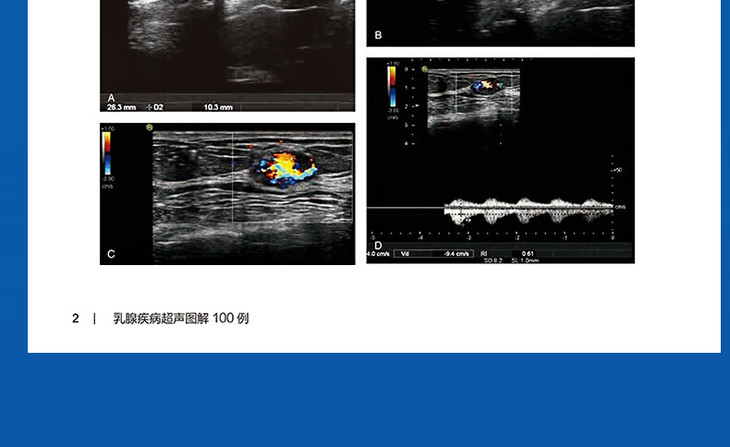

书名:乳腺疾病超声图解100例

通过本书示范性的PBL教学,一方面可以帮助住培生更好的掌握超声知识,助力其成长,在最短的时间获得主动思考的愿望,激发强烈的探究临床疾病超声图像演变的热情,播种成为超声医学中流砥柱未来大师的种子;另一方面也为广大师资提供了重要的参考教材。与PBL教学乳腺部分相呼应,以100例典型图片入手,简明扼要,结合病史、临床表现,进行图像的分析说明。用大量图片,全面阐述乳腺相关疾病,在短期内实现广大超声住培生对乳腺疾病超声表现的深刻认知。